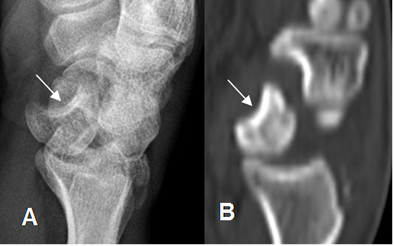

Fig 70. Ruptura del ligamento escafosemilunar.

A: Rx AP y B: TAC reconstrucción coronal. Aumento del espacio escafosemilunar, por lesión ligamentaria.